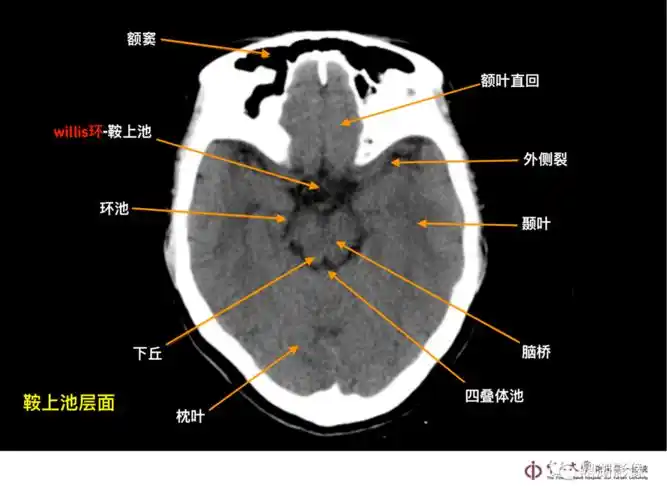

超实用急诊头颅ct3b阅片法